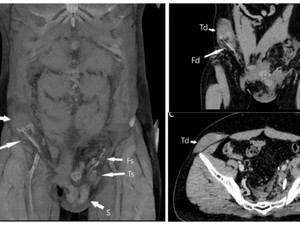

Lebih lanjut, dokter melakukan CT scan untuk menemukan lokasi testis yang telah berpindah tempat. Hasilnya, testisnya berpindah tempat jauh ke perut kanannya.

Pria yang tak disebutkan identitasnya itu awalnya mengalami kecelakaan motor. Hal itu membuat gonad atau kelenjar endokrin keluar dari skrotum dan melewati kanalis inguinalis, yaitu saluran kecil di selangkangan. Sampai akhirnya menetap di perut.

Dokter kemudian melakukan penanganan dengan menghangatkan testis yang kekurangan oksigen itu. Juga, mulai mengembalikan organ tersebut ke dalam soketnya melalui prosedur orkidopeksi, prosedur yang sering digunakan untuk merawat anak-anak yang buah zakarnya tidak turun sepenuhnya selama masa perkembangan.